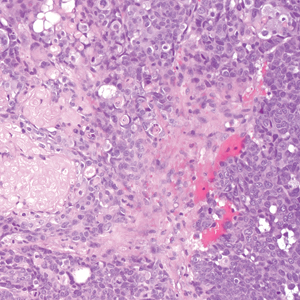

Porocarcinoma is a malignant skin tumor that originates from the intraepidermal sweat gland ducts. It also has been proposed that porocarcinoma develops from benign eccrine poroma. Porocarcinoma often is seen in elderly individuals, with a predilection for the lower extremities. Porocarcinoma demonstrates diverse clinical and histopathologic features, which can make diagnosis challenging. Histopathologically, porocarcinoma has an infiltrative growth pattern, with large basaloid epithelial cells that demonstrate ductal differentiation, cytologic atypia, increased mitotic activity, and tumor necrosis (Figure 3). Some porocarcinomas may exhibit squamous-cell, spindle-cell, or clear-cell differentiation. Neoplastic cells stain positive for CEA, EMA, and CD117, which can assist in distinguishing porocarcinoma from cutaneous SCC.5